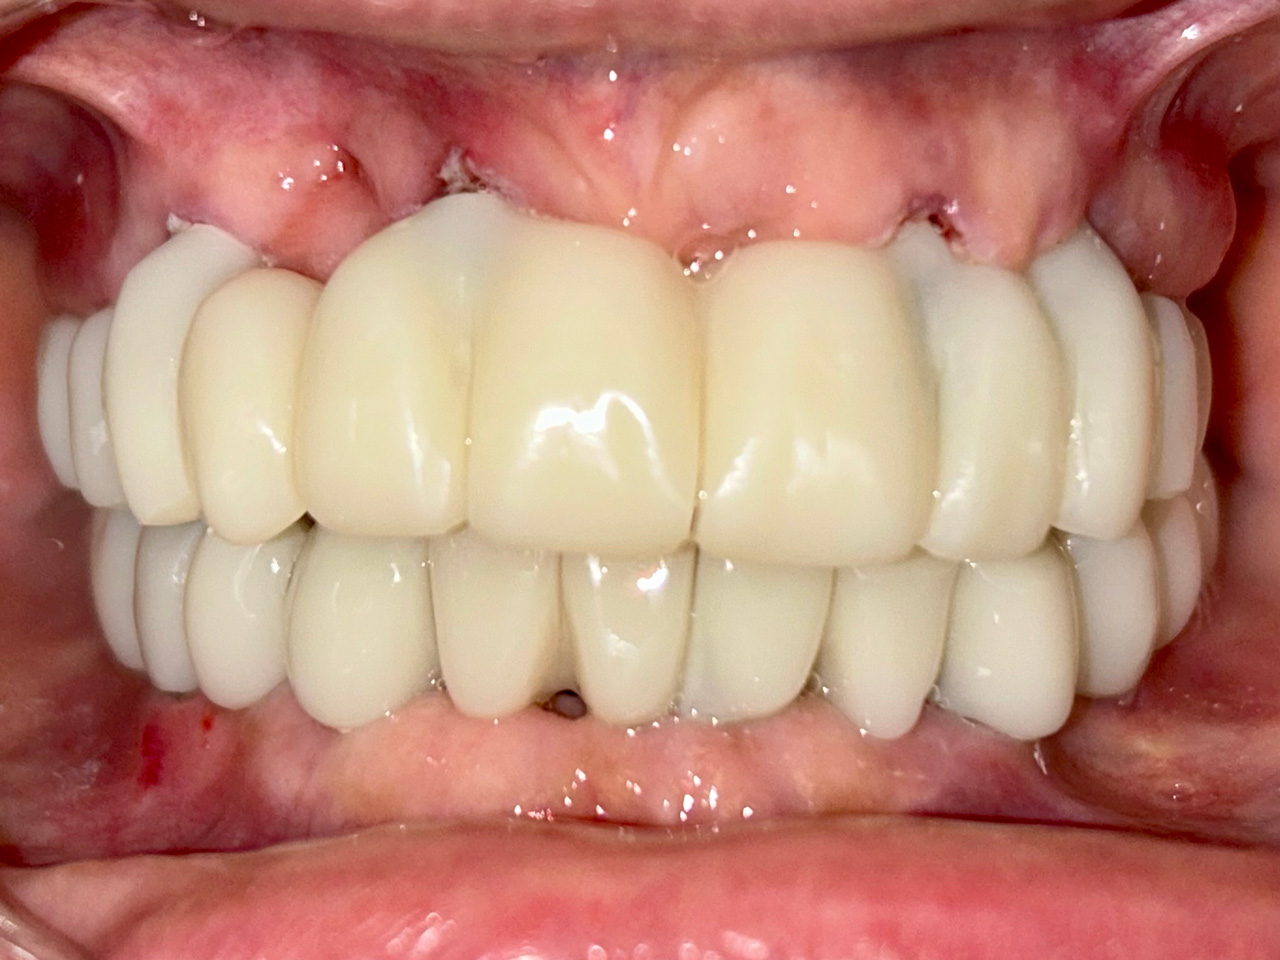

Elhanyagolt fogsor cseréje 2 nap alatt

2 nap alatt varázsoltuk ezt a szép esztétikus alsó, felső körhídat implantátumokkal megtámasztva a korábban elhanyagolt szájba. Az 1. nap 26 fogat távolítottunk el, mert annyira rossz állapotban voltak, és rögtön azonnal terhelhető IHDE svájci implantátumokat raktunk be, fentre 8, lentre 6 darabot. A sebeket összevarrtuk és intraorális szkennerrel digitális lenyomatot vettünk. 2 nap múlva pedig beragasztottuk a kész PMMA műanyag körhidakat. Dr. Kelemen Péter és a Symbion Fogtechnika munkája.